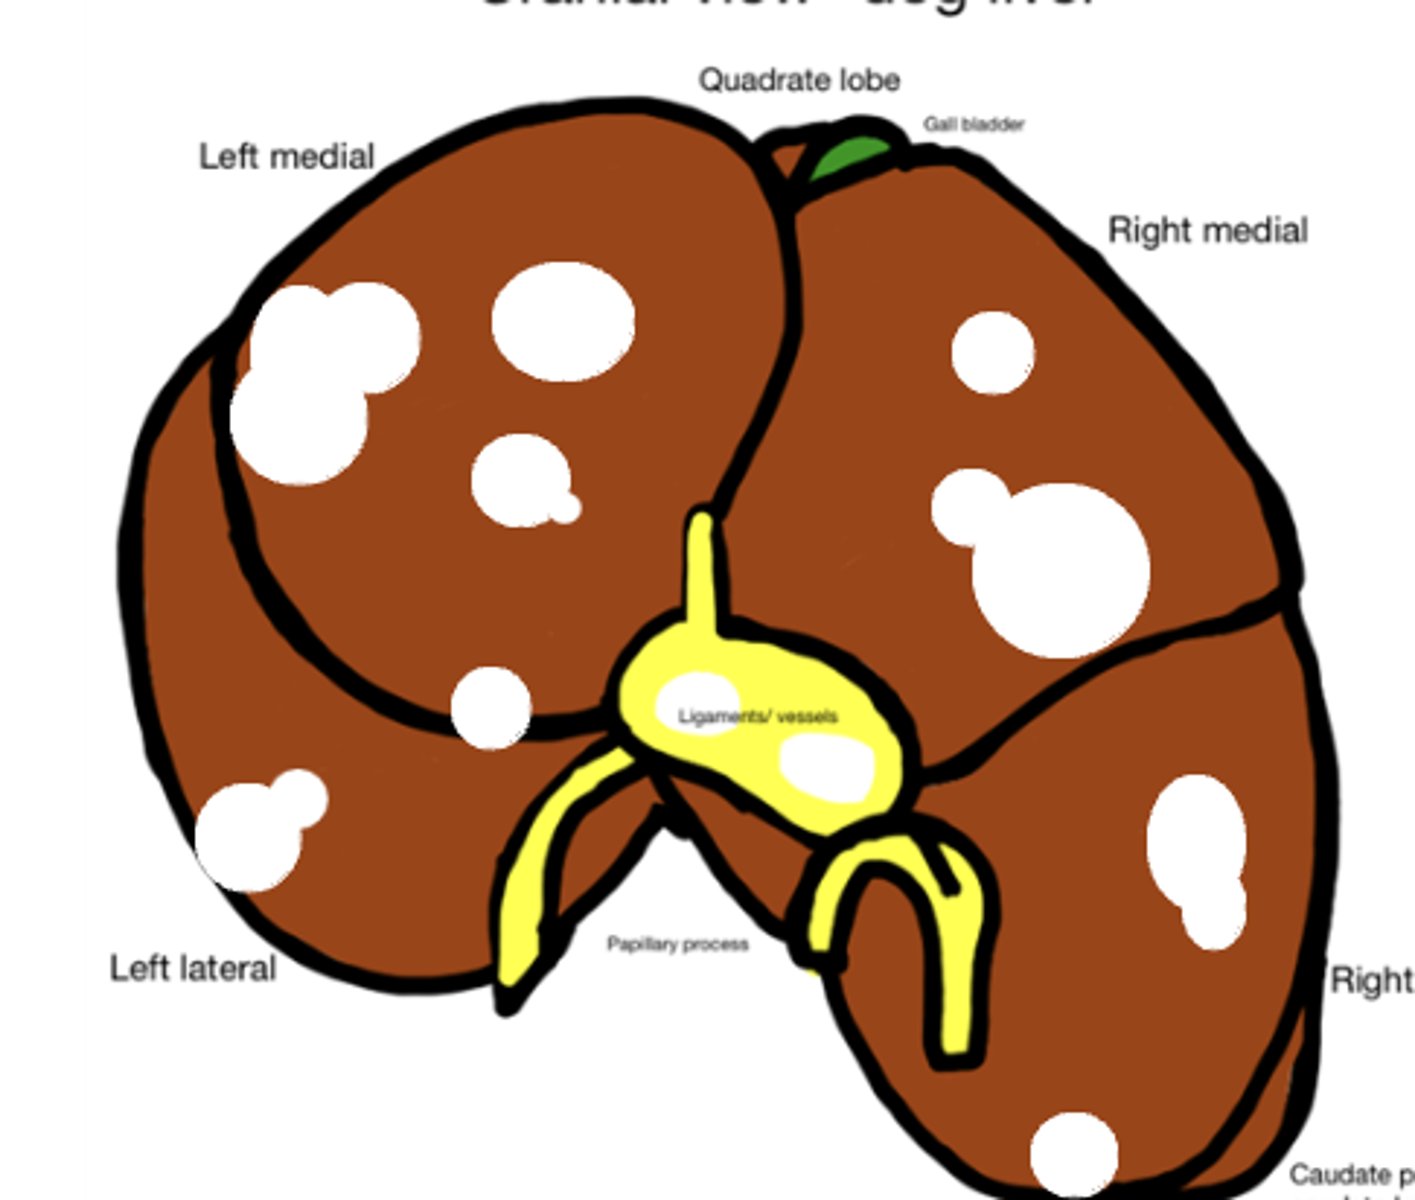

Hepatocellular carcinoma

-firm tissue

-malignant

-

What has caused this gross appearance of this liver?

Hepatocellular carcinoma

What has caused this gross appearance of this liver?